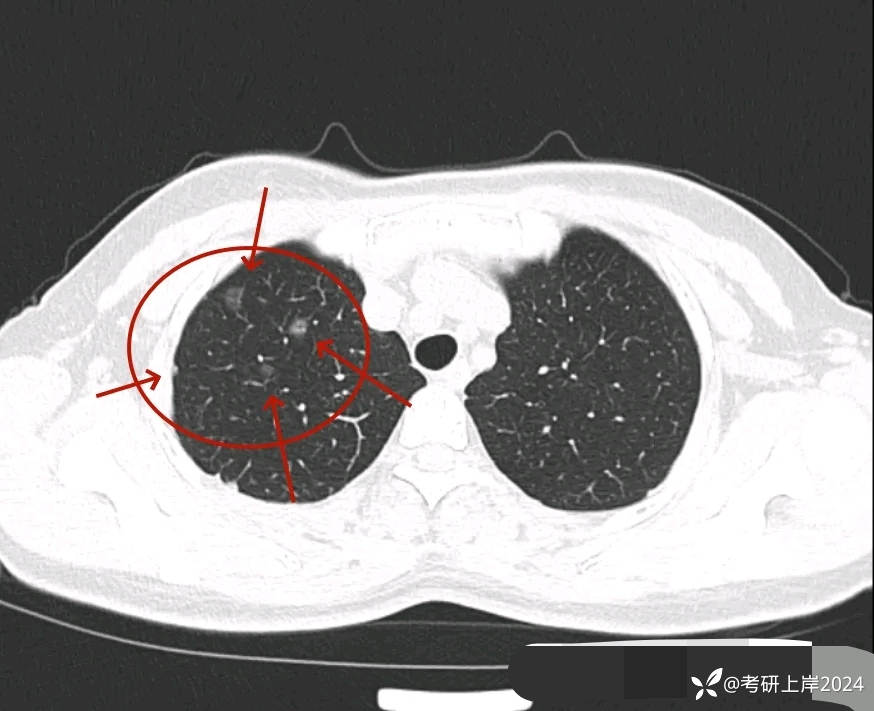

患者最近的检查有AI辅助诊断意见,找出的病灶分别如下:

病灶1:右上叶长径8毫米纯磨玻璃结节,边上有微小血管贴着,整体轮廓较清,怕哪样欠均匀。考虑不典型增生或原位癌可能性大;

病灶2:右上叶长径7毫米磨玻璃结节,密度稍高,但仍未达纵隔窗可见的实性密度,中间有小空泡征,轮廓与边界清,考虑原位癌或微浸润性腺癌可能性较大;

病灶3:右上叶磨玻璃结节伴空泡征,原位癌或不典型增生可能性较大。

病灶4:右上叶磨玻璃结节,密度较淡,有微小血管进入,轮廓较清,考虑肺泡上皮增生或不典型增生可能性大。

病灶5:右上叶微小磨玻璃结节,轮廓较清,考虑肺泡上皮增生可能性较大;

病灶6:左上叶微小磨玻璃结节,轮廓较清,考虑肺泡上皮增生可能性较大;

病灶7:左上叶微小淡磨玻璃结节,考虑少许慢性炎或伴肺泡上皮增生可能性较大;

病灶8:右上叶微小磨玻璃结节,轮廓较清,考虑肺泡上皮增生可能性较大;

病灶9:右上叶磨玻璃结节,轮廓较清,密度稍均,似有微小血管贴边,考虑慢性炎伴肺泡上皮增生可能性较大;

病灶10:左上叶极淡密度的小片状模糊影,少许纤维增生或肺泡上皮增生;

病灶11:左上叶微小磨玻璃结节,轮廓较清,考虑肺泡上皮增生可能性较大;

病灶12:左上叶磨玻璃结节,轮廓较清,有血管穿行,考虑肺泡上皮不典型增生可能性较大,也可能原位癌;

病灶13:左下叶微小磨玻璃结节,边缘欠清,病灶过小,考虑少许纤维增生或肺泡上皮增生可能性较大;

病灶14:右上叶很淡密度微小磨玻璃结节,轮廓较清,考虑肺泡上皮增生可能性较大;

病灶15:左上叶微小磨玻璃结节,轮廓较清,紧贴叶间裂,考虑肺泡上皮增生可能性较大;

病灶16:右肺磨玻璃结节,伴小空泡征,密度略高但未达实性,考虑原位癌或微浸润性腺癌可能性大;

病灶17:左上叶磨玻璃结节,伴小空泡征,也有微血管征,考虑原位癌可能性较大。

病灶18:左下叶极淡密度结节,但轮廓却清,考虑肺泡上皮增生可能性大;

病灶19:右中叶微小磨玻璃结节,考虑不典型增生可能性大;

病灶20:右下叶磨玻璃结节,轮廓清楚,有微小血管进入,瘤肺边界清。考虑原位癌或不典型增生可能性大;

病灶21:右下叶磨玻璃结节,轮廓清,考虑不典型增生可能性较大;

病灶22:左下叶贴着叶间裂处密度偏高微小结节,良性可能性稍大,因其密度显高,轮廓与边界显糊,又在叶裂处。

病灶23:右中叶极淡密度微小片状影,肺泡上皮增生可能;

病灶24:右下叶叶裂处结节,实性,边缘光滑,没有收缩力,密度过高,考虑肺内淋巴结或碳沫沉积可能性大。2023年12月最明显的结节形态: